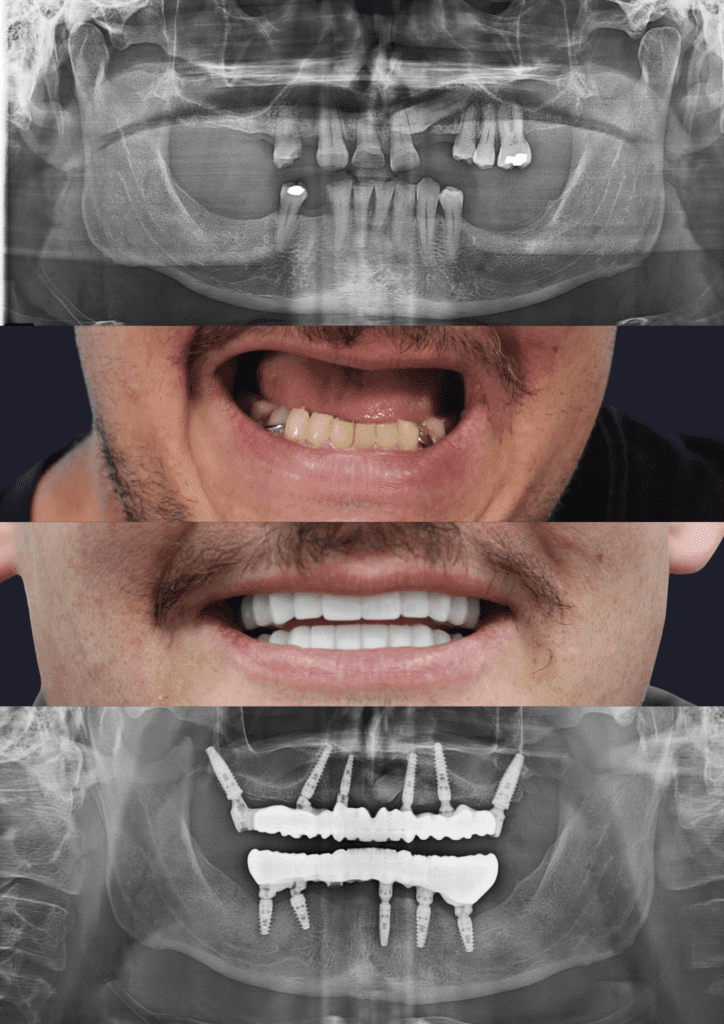

Before & After Treatment Gallery

The photos shown here document completed full-jaw implant treatments. Each case involved detailed planning, surgical placement of implants, and a custom-made fixed bridge. Treatment outcomes, timelines, and suitability vary and are assessed on a case-by-case basis.